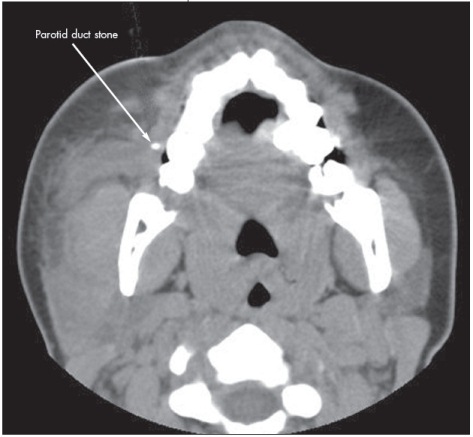

Facial CT scan as shown.

Facial CT revealed a 3-mm calcification in the distal portion of the parotid duct, diffuse enlargement of the parotid gland, and regional lymph node enlargement. After a dose of ampicillin/sulbactam, the patient was discharged with pain medication and a prescription for oral antibiotics. She was advised to apply warm compresses and to suck on sialogogues (sour candy). Follow-up with an otolaryngologist in 7 days was also recommended.